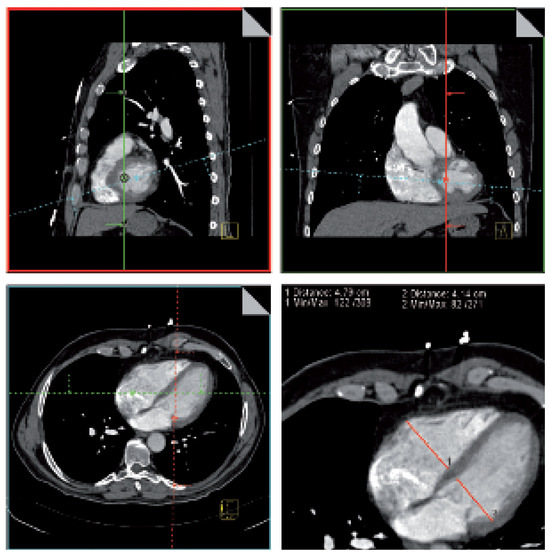

Valve Prosthesis in the Tricuspid Position: An Useasy Relationship

by P. Trigo Trindade, J. Sierra and C. Vuille

Cardiovasc. Med. 2006, 9(4), 167; https://doi.org/10.4414/cvm.2006.01163 - 28 Apr 2006

Case report. A27-year-old woman from Madagascar was referred to our institution because of right heart failure [...] Full article